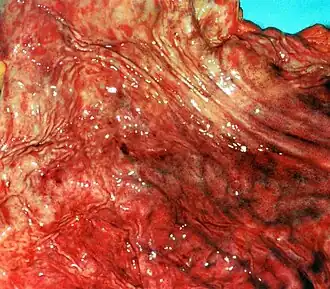

Гастри́т (лат. gastritis, от др.-греч. γαστήρ [gaster] «желудок» + суффикс -itis «воспаление») — воспалительные и дистрофические изменения слизистой оболочки желудка, возникшие по различным причинам[2].

Острым гастритом называют острое воспаление слизистой оболочки желудка, вызванное разовым или непродолжительным воздействием сильных раздражителей. Острый гастрит часто развивается вследствие попадания в желудок раздражающих веществ, например, некоторых лекарств, или после употребления некачественной пищи[3]. Кроме того, острый гастрит может возникать и на фоне других общих заболеваний, часто — при острых инфекциях или нарушениях обмена веществ.

• Коррозийный гастрит (лат. gastritis corrosiva), некротический гастрит или токсико-химический гастрит возникает из-за попадания в желудок концентрированных кислот, концентрированных растворов щёлочей или солей тяжёлых металлов. Он характеризуется некротическими изменениями тканей желудка[13].